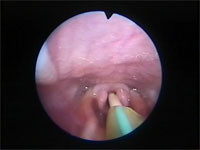

Abb 15 Mandrin-vor-Rima

Abbildung 15: Mandrin vor der fast geschlossenen Rima glottidis.

Abb 16 Mandrin-überwindet-Rima

Abbildung 16: Mandrin hat die Stimmritze passiert und wird intratracheal vorgeschoben.

Über diesen Mandrin kann im zweiten Schritt ein ebenfalls mit wenig Lidocain-Gel präparierter Plastiktrachealtubus von 2,5 bis 3,5 mm innerem Durchmesser behutsam vorgeschoben werden, wobei die vorsichtige Passage der Plica vocalis ohne Schwierigkeiten gelingt.

Abb 17 Vorschieben-des-Tracheotubu

Abbildung 17: Der über den Mandrin gefädelte Tracheotubus ist mit Xylocain®-Gel bestrichen und wird behutsam durch die Stimmfalte vorgeschoben

Nach Ziehen des Mandrins ist die Intubation bewerkstelligt und die Verlegung der Atemwege beseitigt.

Abb 18 Tracheotubus-in-Trachea

Abbildung 18: Tracheotubus in Endlage. Der Mandrin ist entfernt. Man erkennt das laryngospasmusbedingte enge Anliegen der Plica vocalis am Tubus.